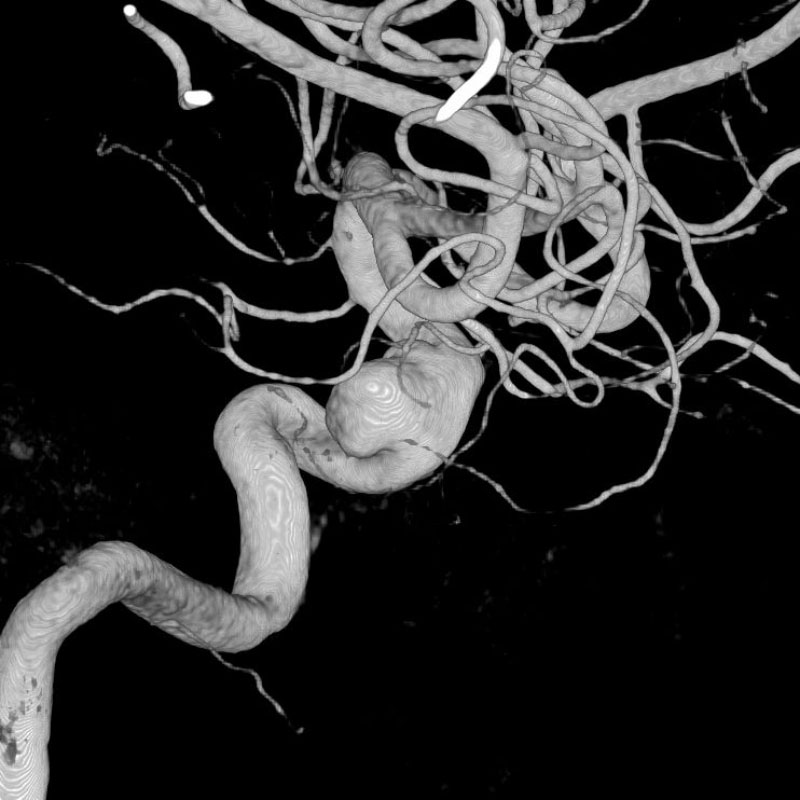

脳動静脈奇形

血管塞栓術

芝野/古谷